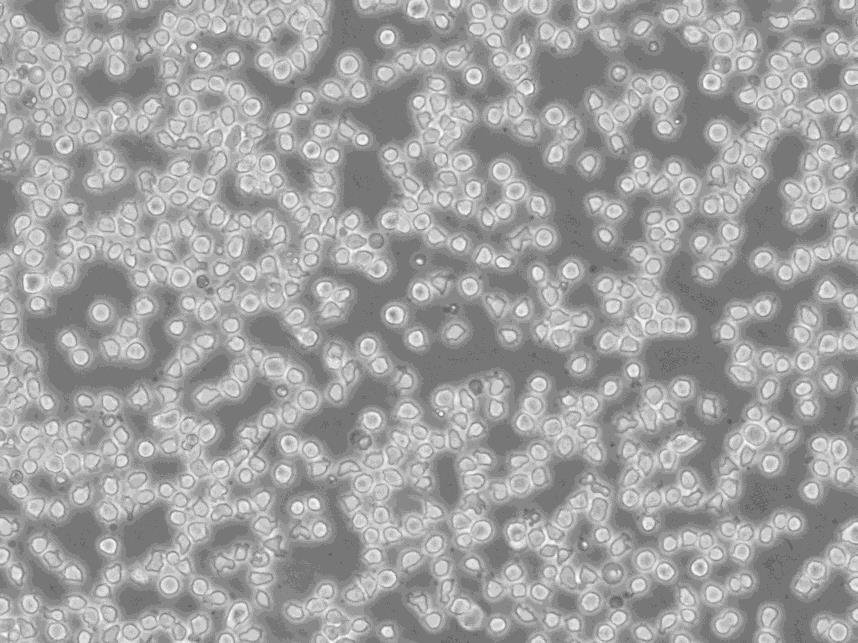

细胞别名:OCI-Aml-3; OCI/AML-3; OCI-AML3; OCI/AML3; OCI AML3; OCIAML3; Ontario Cancer Institute-Acute Myeloid Leukemia-3

生长特性:悬浮生长

形态特性:淋巴母细胞样